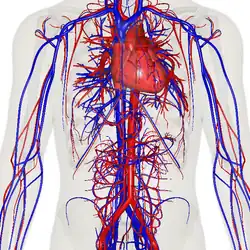

Кровеносная система человека. Красным обозначены артерии, синим — вены. Капиляры соединяют артерии с венами. | |

Циркулято́рная система, также система кровообращения и кровеносная система[1] — система органов, включающая сердце, кровеносные сосуды и кровь, которая циркулирует по всему телу человека или другого позвоночного[2][3]. Включает в себя сердечно-сосудистую систему (также кардио-васкулярная система от греческого kardia — сердце, и латинского vascula — сосуды), которая состоит из сердца и кровеносных сосудов. Кровеносная система состоит из большого и малого круга кровообращения[4].

Сеть кровеносных сосудов составляют магистральные сосуды сердца, включающие крупные артерии и вены, другие артерии и артериолы, а также капилляры, впадающие в венулы (мелкие вены), и другие вены. Кровеносная система у позвоночных замкнута, это значит, что кровь никогда не покидает сеть кровеносных сосудов. Некоторые беспозвоночные, такие как членистоногие, имеют открытую систему кровообращения. У диплобластов, таких как губки и гребневики, кровеносная система отсутствует.

Система кровообращения включает сердце, кровеносные сосуды и кровь[3]. Сердечно-сосудистая система у всех позвоночных состоит из сердца и сосудов. Кровеносная система делится на два основных контура — малый и большой круги кровообращения[2][4]. Малый круг кровообращения представляет собой контурную петлю от правого желудочка, по которой кровь поступает в легкие, где она насыщается кислородом и возвращается в левый желудочек. Большой круг кровообращения доставляет насыщенную кислородом кровь от левого желудочка к остальной части тела и возвращает кровь обратно в правый желудочек через крупные вены, известные как полые вены. Циркуляцию крови также можно разделить на две части — макроциркуляцию и микроциркуляцию. В среднем у взрослого человека содержится от пяти до шести литров крови, что составляет примерно 7 % от общей массы тела[9]. Кровь состоит из плазмы, эритроцитов, лейкоцитов и тромбоцитов . Пищеварительная система также работает совместно с системой кровообращения, обеспечивая организм питательными веществами, необходимыми для поддержания работы сердца[10].